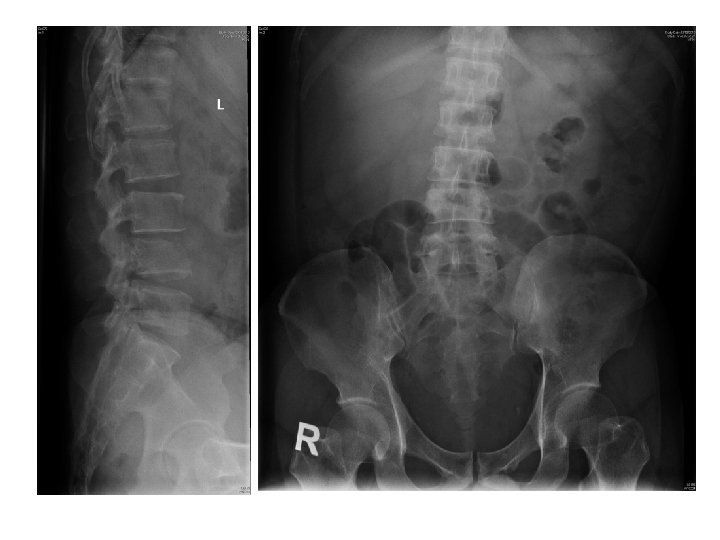

Case 4 • • • M/40 IVDA Personality disorder c/o LBP for 3 days

Case 4 • • • M/40 IVDA Personality disorder c/o LBP for 3 days No injury Could not walk

Questions • What were the red flags of LBP?

• What were the X ray findings? • What were the differential diagnosis?

• What were the X ray findings? • What were the differential diagnosis? • What other imaging Ix you would consider?

• How to manage this patient?